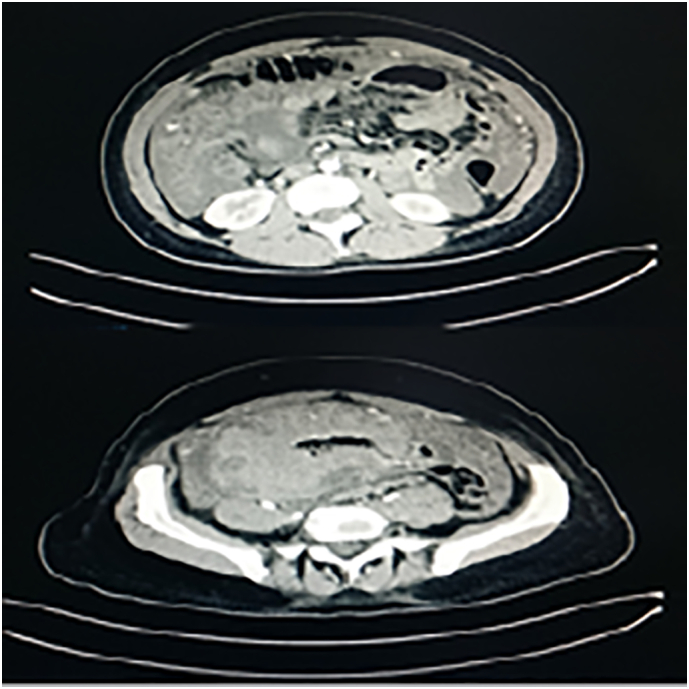

During her stay, the patient underwent a rectosigmoidoscopy, that excluded the presence of malignant colonic lesions. In addition, a thoracoabdominal CT scan was performed, revealing the presence of ascites, omental cake appearance of the greater omentum, and a voluminous meso-hypogastric and pelvic mass encasing ileum and cecum with inhomogeneity of uterus and left ovary (Fig. 1).

Fig. 1.

CT scan revealed a voluminous mass that include bowel and features as peritonitis carcinomatosis.